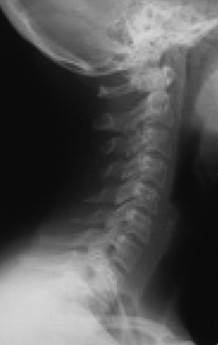

Рис. 12. Правильный физиологический изгиб А=А1 (слева). Гиперлордоз шейного отдела – B больше B1 (справа)

Причем, опять же, рост этого горбика она объясняет исключительно «солями» – остеохондрозом – и не связывает с изменившейся статикой своего позвоночника. В норме позвоночник, как известно, не должен быть прямым, как палка, а иметь физиологические изгибы. В частности, шейный отдел, состоящий из 7 позвонков, в норме должен быть чуть прогнутым внутрь (рис. 13).

Рис. 13. Нормальная статика шейного отдела

Рис. 13а. Спрямление шейного отдела

Рис. 13б. Гиперлордоз шейного отдела